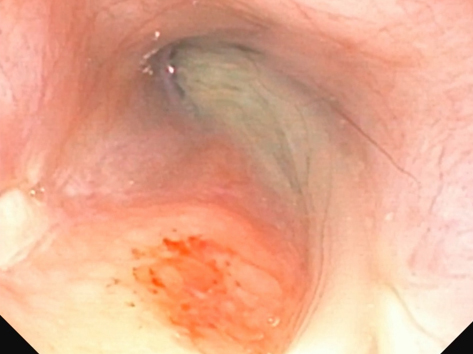

鼻咽頭内視鏡検査

鼻腔内視鏡検査の様子